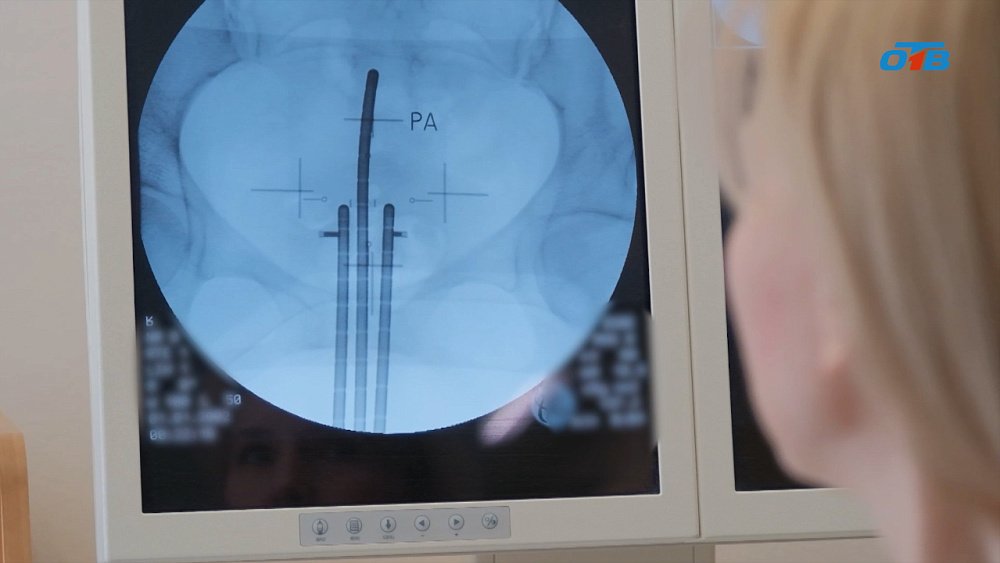

Через специальную трубочку в зону опухоли вводят миниатюрный источник излучения. Он работает как «точечная лампа» — убивает рак, но почти не задевает здоровые органы. Пример из жизни: представьте, что нужно уничтожить сорняк в огороде. Можно поливать ядом весь участок (как обычная лучевая терапия), но тогда пострадают и полезные растения. А можно капнуть яд точно на сорняк — это и есть брахитерапия. Эффективность метода подтверждают цифры: более 400 пациенток в год проходят здесь лечение рака шейки и тела матки. Но как это работает?

«Контактная терапия бывает разной: внутриполостная, внутрипросветная, аппликационная. У нас в отделении чаще используют внутриполостную. Благодаря 3D-планированию обеспечивается персонализированный подход к каждой пациентке», — подчеркнула Мария Ивахно.

«Источник здесь миниатюрный — всего 1 мм в диаметре. С помощью методики автолодинг он перемещается в аппликатор, установленный у пациентки, облучает опухоль и возвращается в хранилище. Весь процесс управляется с пульта — персонал не контактирует с излучением», — отметила Мария Ивахно.